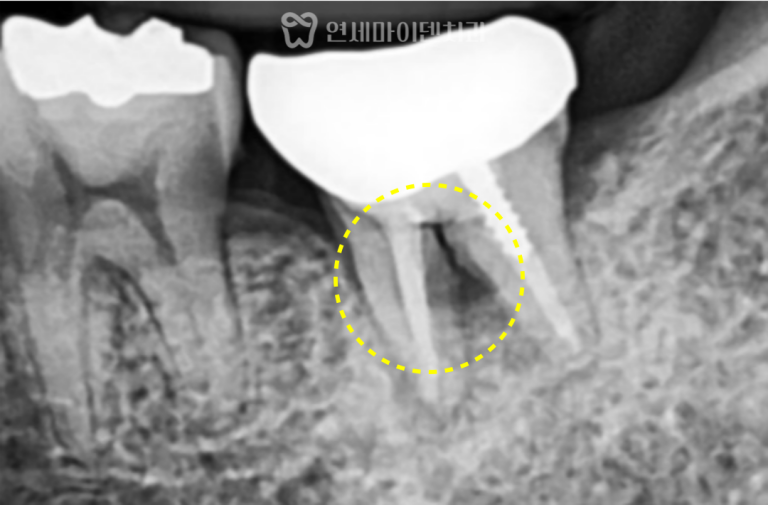

발치즉시 임플란트 증례: 어금니 흔들림 왼쪽 아래 어금니에서냄새가 나고 흔들리는 증상으로내원하신 케이스입니다. 치아를 가능한 한 보존하는…